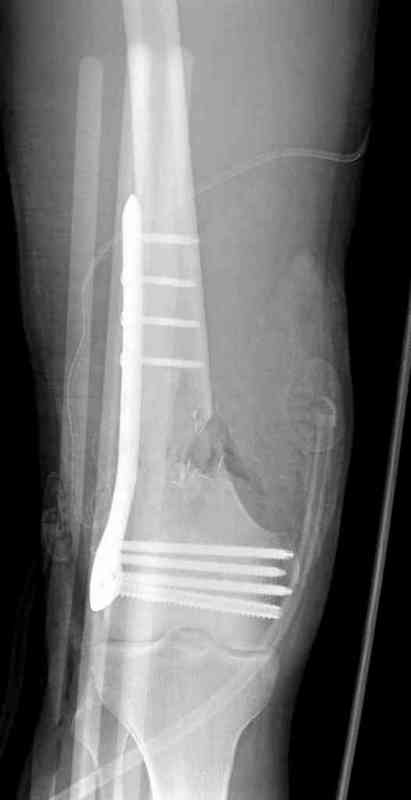

Мне кажется здесь нужна стабильная фиксация пластиной LSP DF или LSP мыщелковй пластиной для дистальной части бедренной кости, выполнить декортикацию,и с целью стимуляции остеогенеза использовать аутокость или chronOS блок

тактика стандартная при атрофических ложных суставах-lcp+костная пластика

атрофический лложный сустав-костная пластика, короткий дистальный отломок,о\пороз,нижняя конечность-lcp

If not and patient is otherwise well: locking distal femoral plate is my first choice.

This is not all that old - only two years. My choice would be to open the fracture site, freshen the ends, get as near an anatomical reduction as possible and use the locking compression plate system for fixation.

I have a similair case who had non -union after supracondylar nail, which broke at the fracture site. I had to take the nail out and then fixed it with LISS_DF (locking plate) I did use the bone graft. fracture healed with 3 months.

Next, anatomic alignment [not necessarily anatomic reduction] and lots of compression. I would use a locking plate with non locking screws proximally to allow that extra compression watching to be sure not to create excessive valgus. I would not worry about length. Bone graft as needed.

My view is that if it is hyper- or normotrophic nonunion, or partial healing i would proceed to gradual correction with ex-fix, then

conversion to a nail (my personal preference would be antegrade nailing though of course retrograde is suitable). In case of atrophic nonunion and loose mobility - site opening + grafting, fixation by a plate with angular stablity.